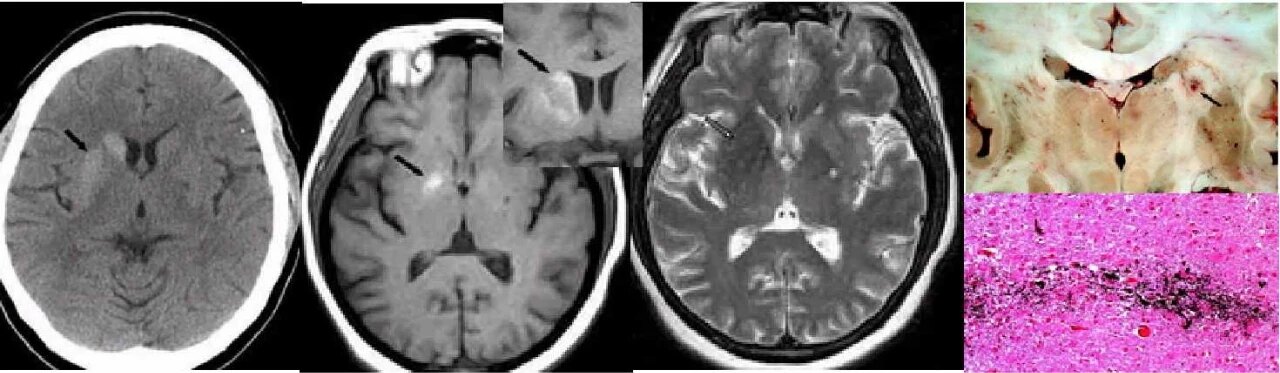

case 2:

女,58 岁,非酮症高血糖性偏侧舞蹈病。CT 示右侧尾状核头及豆状核弥漫性高密度。MRI T1WI 示病灶呈高信号,T2WI 呈低信号,边界清晰。病理切片示右侧基底节出血。